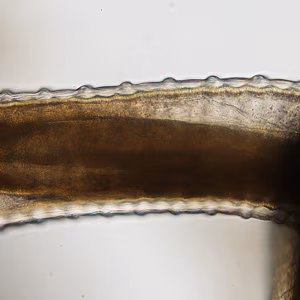

A 25-year-old man sought medical attention for a nodule on his right hand that had developed about a year after returning from travel to Liberia. The nodule was surgically excised and a tangled mass of thin, white worms was observed within. The worms were preserved in 10% formalin and sent to CDC-DPDx for identification. Figure A shows the mass of worms; Figures B and C show what was observed at 100x after partial clearing in lactophenol. What is your diagnosis? Based on what criteria?

Figure B